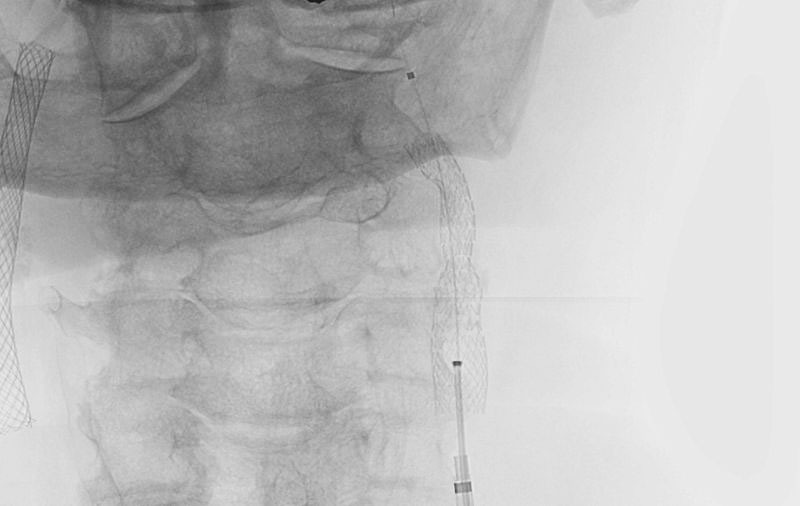

No.1596 手術中